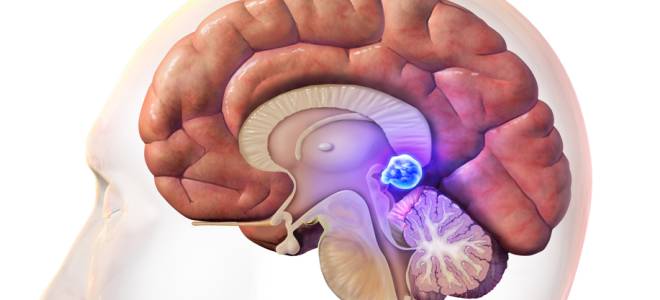

Киста шишковидной железы головного мозга представляет собой полостное образование, заполненное жидкостью, которое образуется в одной из долей этого органа. Шишковидная железа — это небольшой непарный эндокринный орган, расположенный между полушариями мозга, в области межталамического сращения.

Киста шишковидной железы головного мозга, хотя и считается доброкачественной опухолью, может представлять определенные риски для здоровья. Эксперты отмечают, что такие образования могут вызывать различные неврологические симптомы, включая головные боли, нарушения сна и изменения в гормональном фоне. В зависимости от размера кисты и её расположения, возможны компрессия соседних структур и нарушение их функции. Это может привести к проблемам с зрением, координацией и даже к психоэмоциональным расстройствам. Важно, чтобы пациенты проходили регулярные обследования и находились под наблюдением специалистов, чтобы своевременно выявлять изменения в состоянии и принимать необходимые меры. Ранняя диагностика и адекватное лечение могут значительно снизить риск осложнений и улучшить качество жизни.